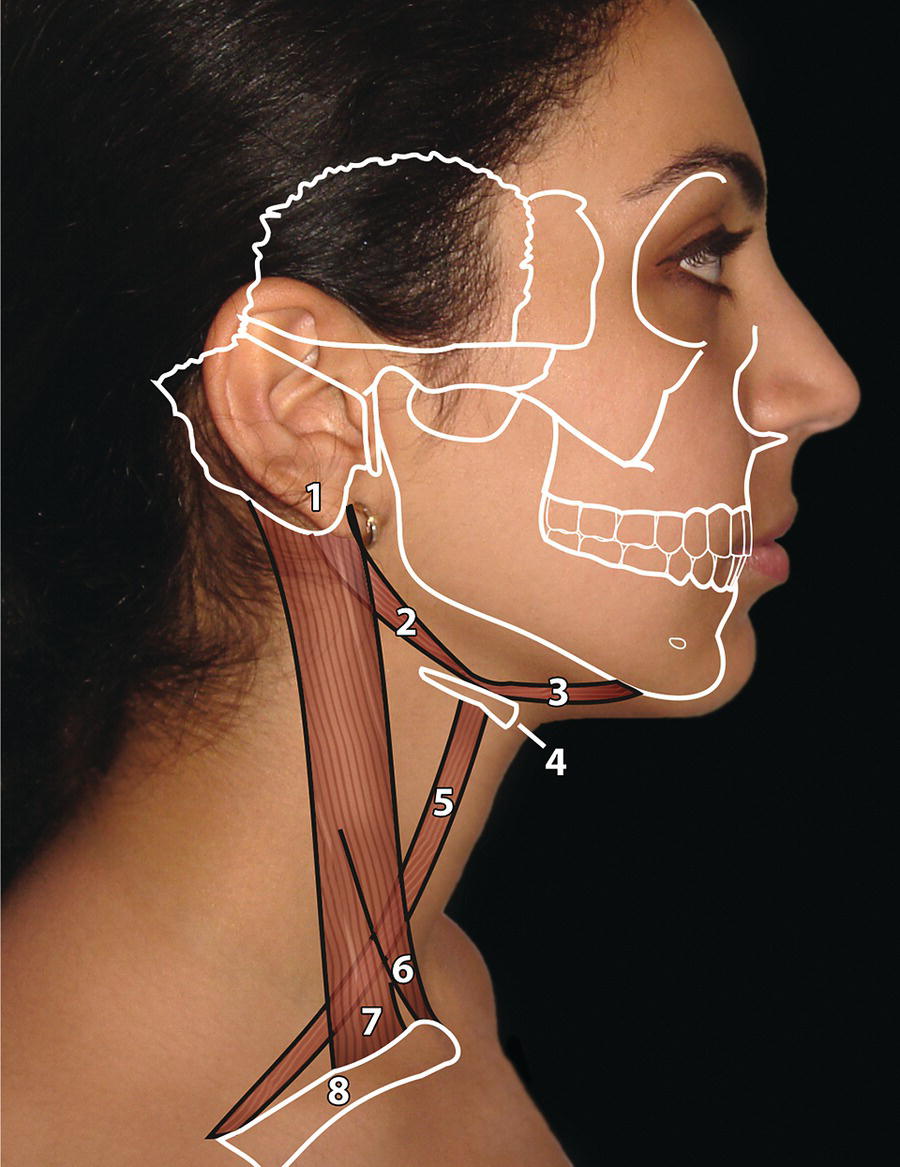

The morphology of the upper aspect of the neck and its transition with the submental region has a major impact on the aesthetics of the lower face. The anterior part of the neck extends no higher than the inferior border of the mandible. The hyoid bone is connected to the mandible by a thin sheet of muscle, the mylohyoids, which form the upper limit of the anterior part of the neck and separate the mouth from the neck. Superficially (i.e. below the mylohyoids) lies the anterior belly of digastric, while lying above it, half hidden under the mandible in the submandibular fossa, is the submandibular salivary gland (Figure 21.1). These structures are covered in by the investing layer of deep cervical fascia, which is attached to the hyoid bone and the inferior border of the mandible. The platysma muscle lies in the subcutaneous tissues. It forms a broad, flat sheet, extending from the deep fascia over the upper part of pectoralis major and the most anterior part of deltoid to the inferior border of the mandible, with some fibres reaching the lateral part of the lower lip. The sternocleidomastoid muscle forms a prominent neck landmark and may be made to stand out by turning the head towards the opposite side against resistance. The two heads of origin are from the sternum and medial one‐third of the clavicle; its attachment is to the mastoid process, which forms a readily visible and palpable bony landmark behind the lobe of the ear (Figure 21.2). Figure 21.1 Submental anatomy in relation to the mandible, with muscle attachments: Despite its importance in facial aesthetics, there is much confusion in terminology relating to the description and analysis of the submental‐cervical region. For example, the cervicomental angle has been described by perhaps half a dozen different methods, depending on the describing authority. Appropriate terminology is essential for the evaluation and accurate description of submental‐cervical aesthetics (Figure 21.3). Figure 21.2 Profile view of the face and neck with superimposed bony and muscular outlines: Cervical point (C‐point or ‘point C’): The innermost (posterior‐superior) point between the submental plane and the anterior aspect of the neck in the midsagittal plane, located at the intersection of lines drawn tangent to the submental region and the anterior neck. Submental plane: A plane or line constructed between the cervical point (C‐point) and the most inferior point on the chin (soft tissue menton, Me’). If C‐point cannot be defined, the submental plane is drawn tangent to the submental contour passing through soft tissue menton. The submental plane is referred to as the ‘throat’ plane by some authorities; the submental length (distance from C‐point to menton) is therefore sometimes referred to as the ‘throat length’. Cervical plane: A plane or line drawn tangent to the anterior soft tissue contour of the neck above and below the thyroid prominence. Figure 21.3 Submental plane, cervical plane and cervical point (C‐point). A thorough understanding of the aetiological factors involved in creating a poor aesthetic contour of the submental‐cervical region is required in order to diagnose and appropriately plan the correction of the aesthetic submental‐cervical angles and contour. The tonicity of the submental‐cervical skin, the muscular support of the neck, the isolated fatty deposits in the submental‐cervical region, the skeletal framework of the mandible and chin, and the spatial position of the hyoid bone are all important parameters in the aesthetic analysis of the submental‐cervical region. An undesirable submental‐cervical contour may result from: It is paramount that the clinical evaluation is undertaken with the patient in natural head position (NHP). Even a small degree of upward or downward tilting of the head must be avoided as it may have a profound effect on the contour of the submental‐cervical region. A number of parameters may be analysed in the clinical evaluation of the submental‐cervical region: Mandibular and/or chin deficiency in the sagittal plane, and/or posterior (downward and backward) rotation of the mandible, often secondary to vertical maxillary excess, may contribute to the undesirable aesthetic appearance of the submental‐cervical region (Figure 21.4). It is helpful to have the ‘Class II skeletal pattern’ patient posture the mandible forward to a more normal sagittal position, which will concurrently stretch the submental soft tissues. If this manoeuvre improves the submental‐cervical aesthetics visually, and tightens the submental soft tissues to palpation, then correction of the underlying skeletal discrepancy is likely to improve the submental‐cervical aesthetics (Figure 21.5). Figure 21.4 Class II jaw relationship due to mandibular deficiency and significant compensatory proclination of the mandibular incisor teeth; the submental‐cervical angle is increased. Figure 21.5 (A) Patient with Class II jaw relationship due to mandibular deficiency. (B) Posturing the mandible forward to a more normal sagittal position will concurrently stretch the submental soft tissues. Figure 21.6 Skin laxity test. The converse is also true. Surgical procedures to set back the mandible, or set down the maxilla causing posterior mandibular rotation, will tend to have undesirable consequences on submental‐cervical aesthetics (see Figure 19.22). The patient must be informed of these potential untoward consequences of orthognathic surgery, and should be advised of the possible future need for aesthetic surgical procedures of the submental‐cervical region. The laxity of the submental‐cervical skin may be evaluated by the skin laxity test: the clinician stands behind the patient and gently pulls the soft tissues upward and backward just inferior and anterior to the ear, simulating a neck lift (Figure 21.6). If the soft tissues are easily displaced upward there is increased laxity of the skin, termed redundant skin.1 If following this manoeuvre there is still submental fullness, the patient has redundant skin and excessive submental‐cervical adiposity. Reduced tonicity of the platysma may contribute significantly to submental fullness.2,3 In addition, the platysma muscle may or may not merge anatomically across the midline. Frequently, excessive submental fullness results not only from redundant skin but from the redundant medial borders of the platysma muscle that fail to meet in the midline. Increased submental‐cervical fat accumulation may be independent of generalized body fat; in some patients subcutaneous fat accumulation in this region may remain despite extensive weight loss. In younger patients the fat usually accumulates between the skin and the platysma muscle. In older patients, the fat may accumulate both deep and superficial to the platysma (Figure 21.9). The quantity of submental fat may be estimated by the submental pinch test: the submental soft tissues are gently gripped between the thumb and index finger.1 This manoeuvre should be performed with the patient both in NHP and with the head extended and contracting the platysma muscle; in this way the clinician may determine whether the submental fat is predominantly supraplatysmal or subplatysmal. Figure 21.7 Platysma view: With the head tilted slightly back in frontal view, grimacing and clenching the teeth will induce contraction of the platysma muscle. The muscular fascicles of the platysma become visible beneath the skin. Figure 21.8 Platysmal bands may be evident in repose in an ageing neck. Figure 21.9 Submental adiposity. Figure 21.10 The definition of the inferior border of the mandible is an important aesthetic parameter as it defines the demarcation between the face and neck. (Detail, Woman’s Head, Leonardo da Vinci, c. 1470–76, Galleria degli Uffizi, Florence.) The definition of the inferior border of the mandible, from the chin to the gonial angle, is an important aesthetic parameter, as it defines the demarcation between the face and neck (Figure 21.10). In frontal view, the transition from the upper aspect of the neck to the inferior border of the mandible has a subtle hourglass appearance, with its superior aspect being well defined by the concavity immediately below the inferior mandibular borders (Figure 21.11).1 The soft tissues of the neck normally closely adhere to the structures underlying them. Lack of definition of the inferior mandibular border may be due to increased soft tissue laxity, fat accumulation, mandibular/chin deficiency or hyoid bone sag. Figure 21.11 In frontal view, the transition from the upper aspect of the neck to the inferior border of the mandible has a subtle hourglass appearance. The submandibular salivary gland envelopes the posterior border of the mylohyoid muscle, half hidden in the submandibular fossa on the medial aspect of the mandible (see Figure 21.1). Submandibular fullness may result from an increase in size of the submandibular gland, laxity of the neck fascial layer or submandibular gland ptosis. Rhytidectomy and platysma plication address this problem indirectly by increasing the fascial support for the gland. However, patients may develop a more noticeable submandibular fullness as the removal of submental fat unmasks the ptotic gland. Partial or complete submandibular gland resection provides definite improvement of submandibular fullness resulting from glandular hypertrophy or ptosis, but may be considered too radical for a patient with a normal‐sized, ptotic submandibular gland. Guyuron et al.4 have described the basket submandibular gland suspension technique, directly supporting the gland onto the inner aspect of the inferior surface of the mandible with a strong piece of fascia. This technique helps eliminate submandibular fullness in patients with normal‐sized, ptotic glands. Resection remains the treatment of choice for the correction of glandular hypertrophy. Figure 21.12 Of the ‘six visual criteria’ of the profile view for ‘success in restoring the youthful neck’, the following are demonstrated: 1 Distinct inferior mandibular border 4 Visible anterior border of sternocleidomastoid muscle 5 Submental‐cervical (submental‐neck) angle between 105° and 120° 6 Sternocleidomastoid‐submental plane (SM‐SM) angle approximately 90°